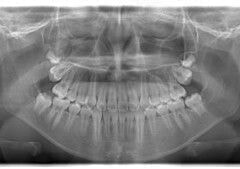

症例紹介

小児期ケース:反対咬合+上顎両側3番埋伏歯

(受け口+右上3番目の永久歯が埋まってしまい、はえてこない)

治療法:上顎急速拡大装置+クリアスナップ+フェイスマスク+上顎右側3番は開窓萌出誘導